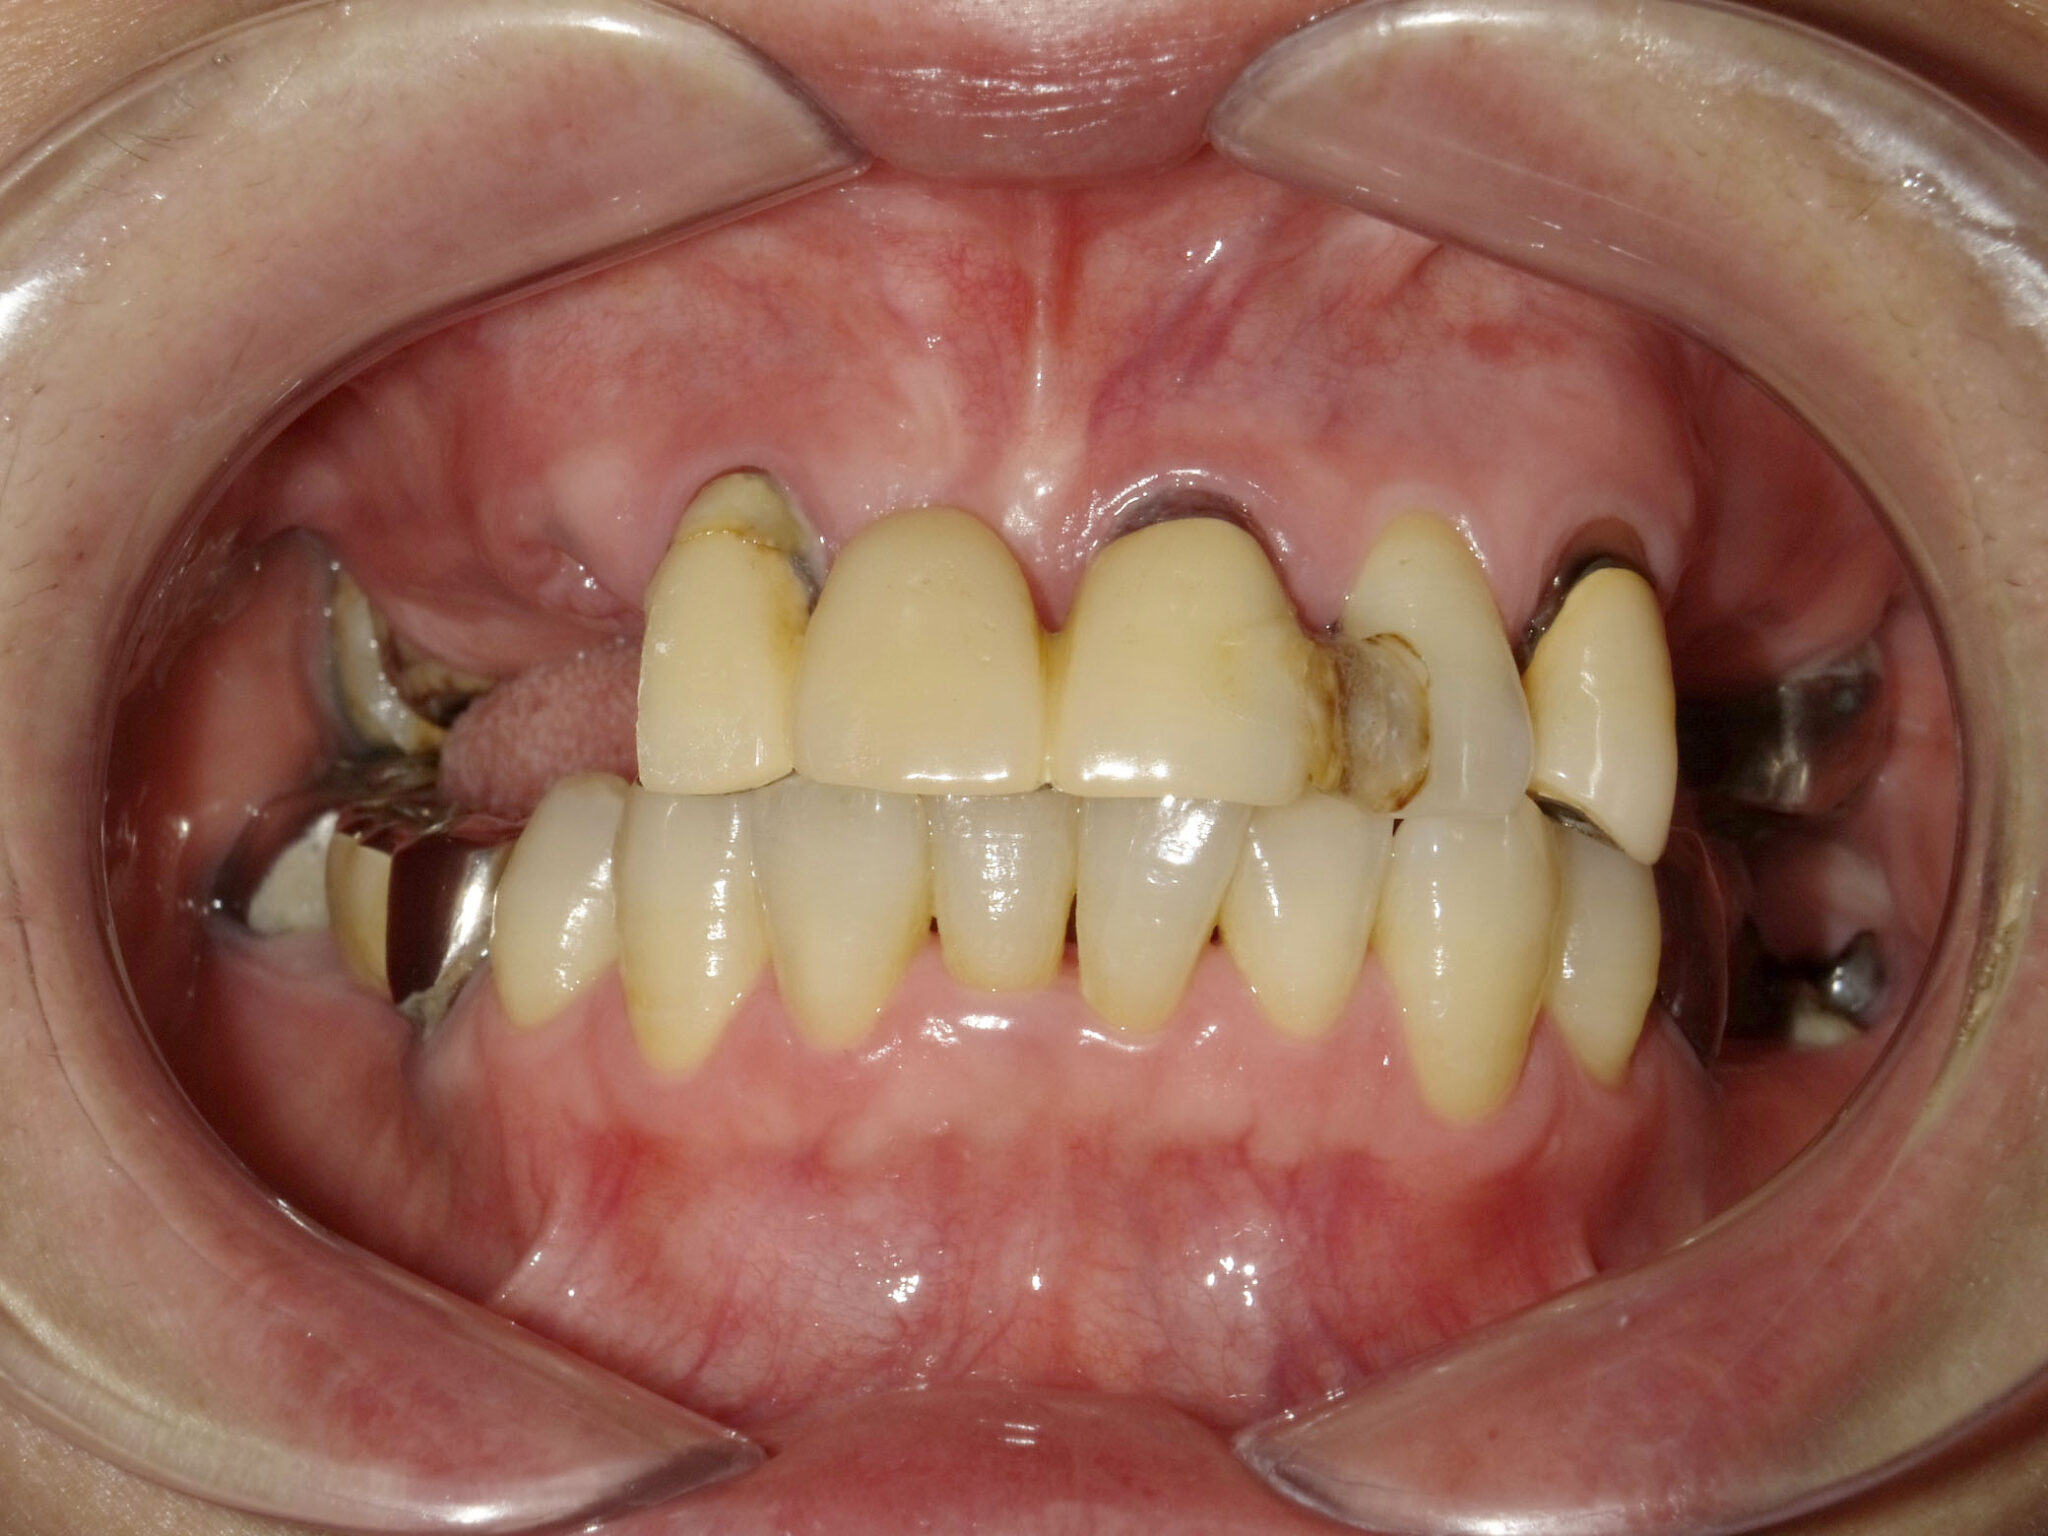

全顎治療症例

| 主訴 | 全体的に見た目を綺麗にしたい。奥歯でしっかり噛みたい。 |

| 診断名・ 主な症状 |

臼歯部欠損 |

| 年齢 | 70歳 |

| 治療内容 | インプラント埋入(右上4・6,左上4・6,右下6,左下6) ジルコニアBr(右上3―左上3) ジルコニア(右下5,左下5) |